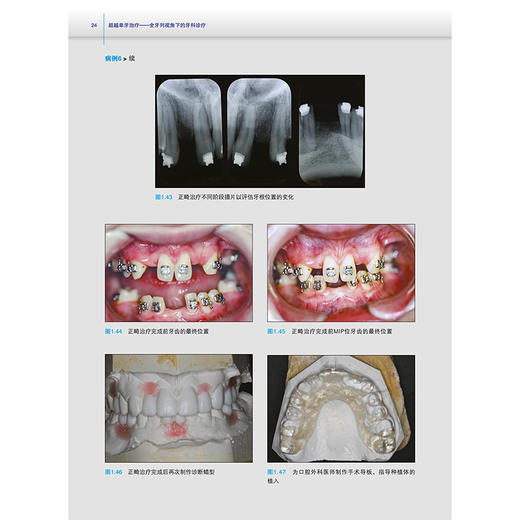

如果您有以上困惑,本书就是您的临床帮手!它能帮您突破“单一学科牙科学”局限,升级为“跨学科牙科学”,联合多学科有序协作,为患者提供全面诊断并制订综合治疗计划。全书共8章,搭配21个典型病例、大量高清图片及10余份详细表格,系统讲解全面诊断、综合治疗计划制定、多学科协作团队组建,助您掌握跨学科牙科诊疗,为临床工作带来新启发。